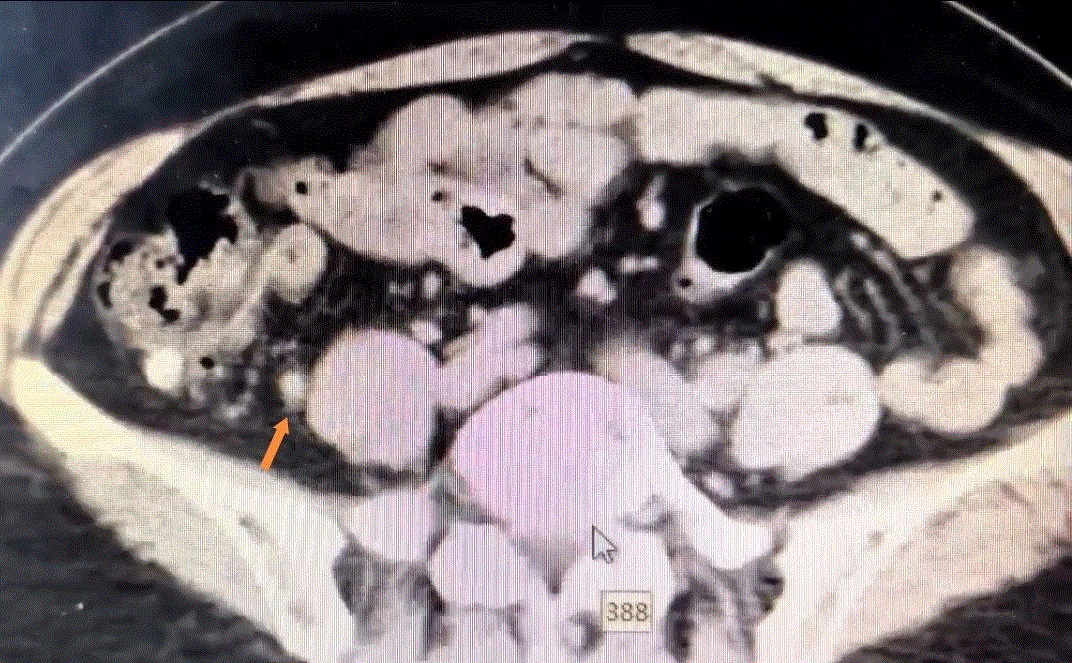

CT检查结果显示,孙阿姨阑尾腔存在粪石,医生初步判断其腹痛原因极有可能是阑尾粪石所致。考虑到孙阿姨的年龄及身体状况,若采用传统手术,孙阿姨需承受较大创伤,术后恢复也需要较长时间。经过普外科诊疗中心王大巍主任及窥镜室姜敏主任医师团队的详细评估,决定为孙阿姨实施内镜逆行阑尾炎治疗术(ERAT)。

术中,窥镜室于笑洋副主任利用结肠镜通过自然腔道到达阑尾开口部位,通过一次性导管成像系统,小心翼翼地插入阑尾腔,完成取石、冲洗、引流、减压等操作,阑尾粪石梗阻被成功解除。术后,孙阿姨的腹痛症状迅速缓解。